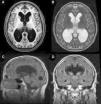

La hidrocefalia crónica del adulto idiopática (HCAi) es una entidad nosológica caracterizada por la tríada clínica de trastorno de la marcha, deterioro cognitivo e incontinencia urinaria, en presencia de dilatación del sistema ventricular en las pruebas de neuroimagen (fig. 1) y en ausencia de otra causa que justifique los hallazgos clínicos.

Resonancia magnética preoperatoria de un paciente diagnosticado de hidrocefalia crónica del adulto idiopática con buena respuesta tras la implantación de una derivación ventrículo-peritoneal. A) Corte axial potenciado en T1. Moderada dilatación de los ventrículos laterales y del tercer ventrículo. B) Corte axial potenciado en T2. Artefactos de señal por vacío de flujo en el tercer ventrículo y ausencia de hiperintensidades de señal tanto a nivel periventricular como subcortical. C) Corte sagital potenciado en T1. Descenso del suelo y abalonamiento del tercer ventrículo, con reducción de la distancia mamilo-pontina. El acueducto de Silvio se encuentra permeable, sin que se visualicen causas obstructivas que justifiquen la dilatación ventricular. D) Corte coronal FLAIR. Patrón típico de borramiento de surcos en la convexidad alta del cerebro, especialmente en la línea media. El artefacto por vacío de flujo que se objetivaba en la secuencia T2 se extiende hacia ambos agujeros de Monro, alcanzando la porción inferior y medial de los cuerpos ventriculares. Ausencia de hiperintensidades de señal periventriculares y subcorticales.